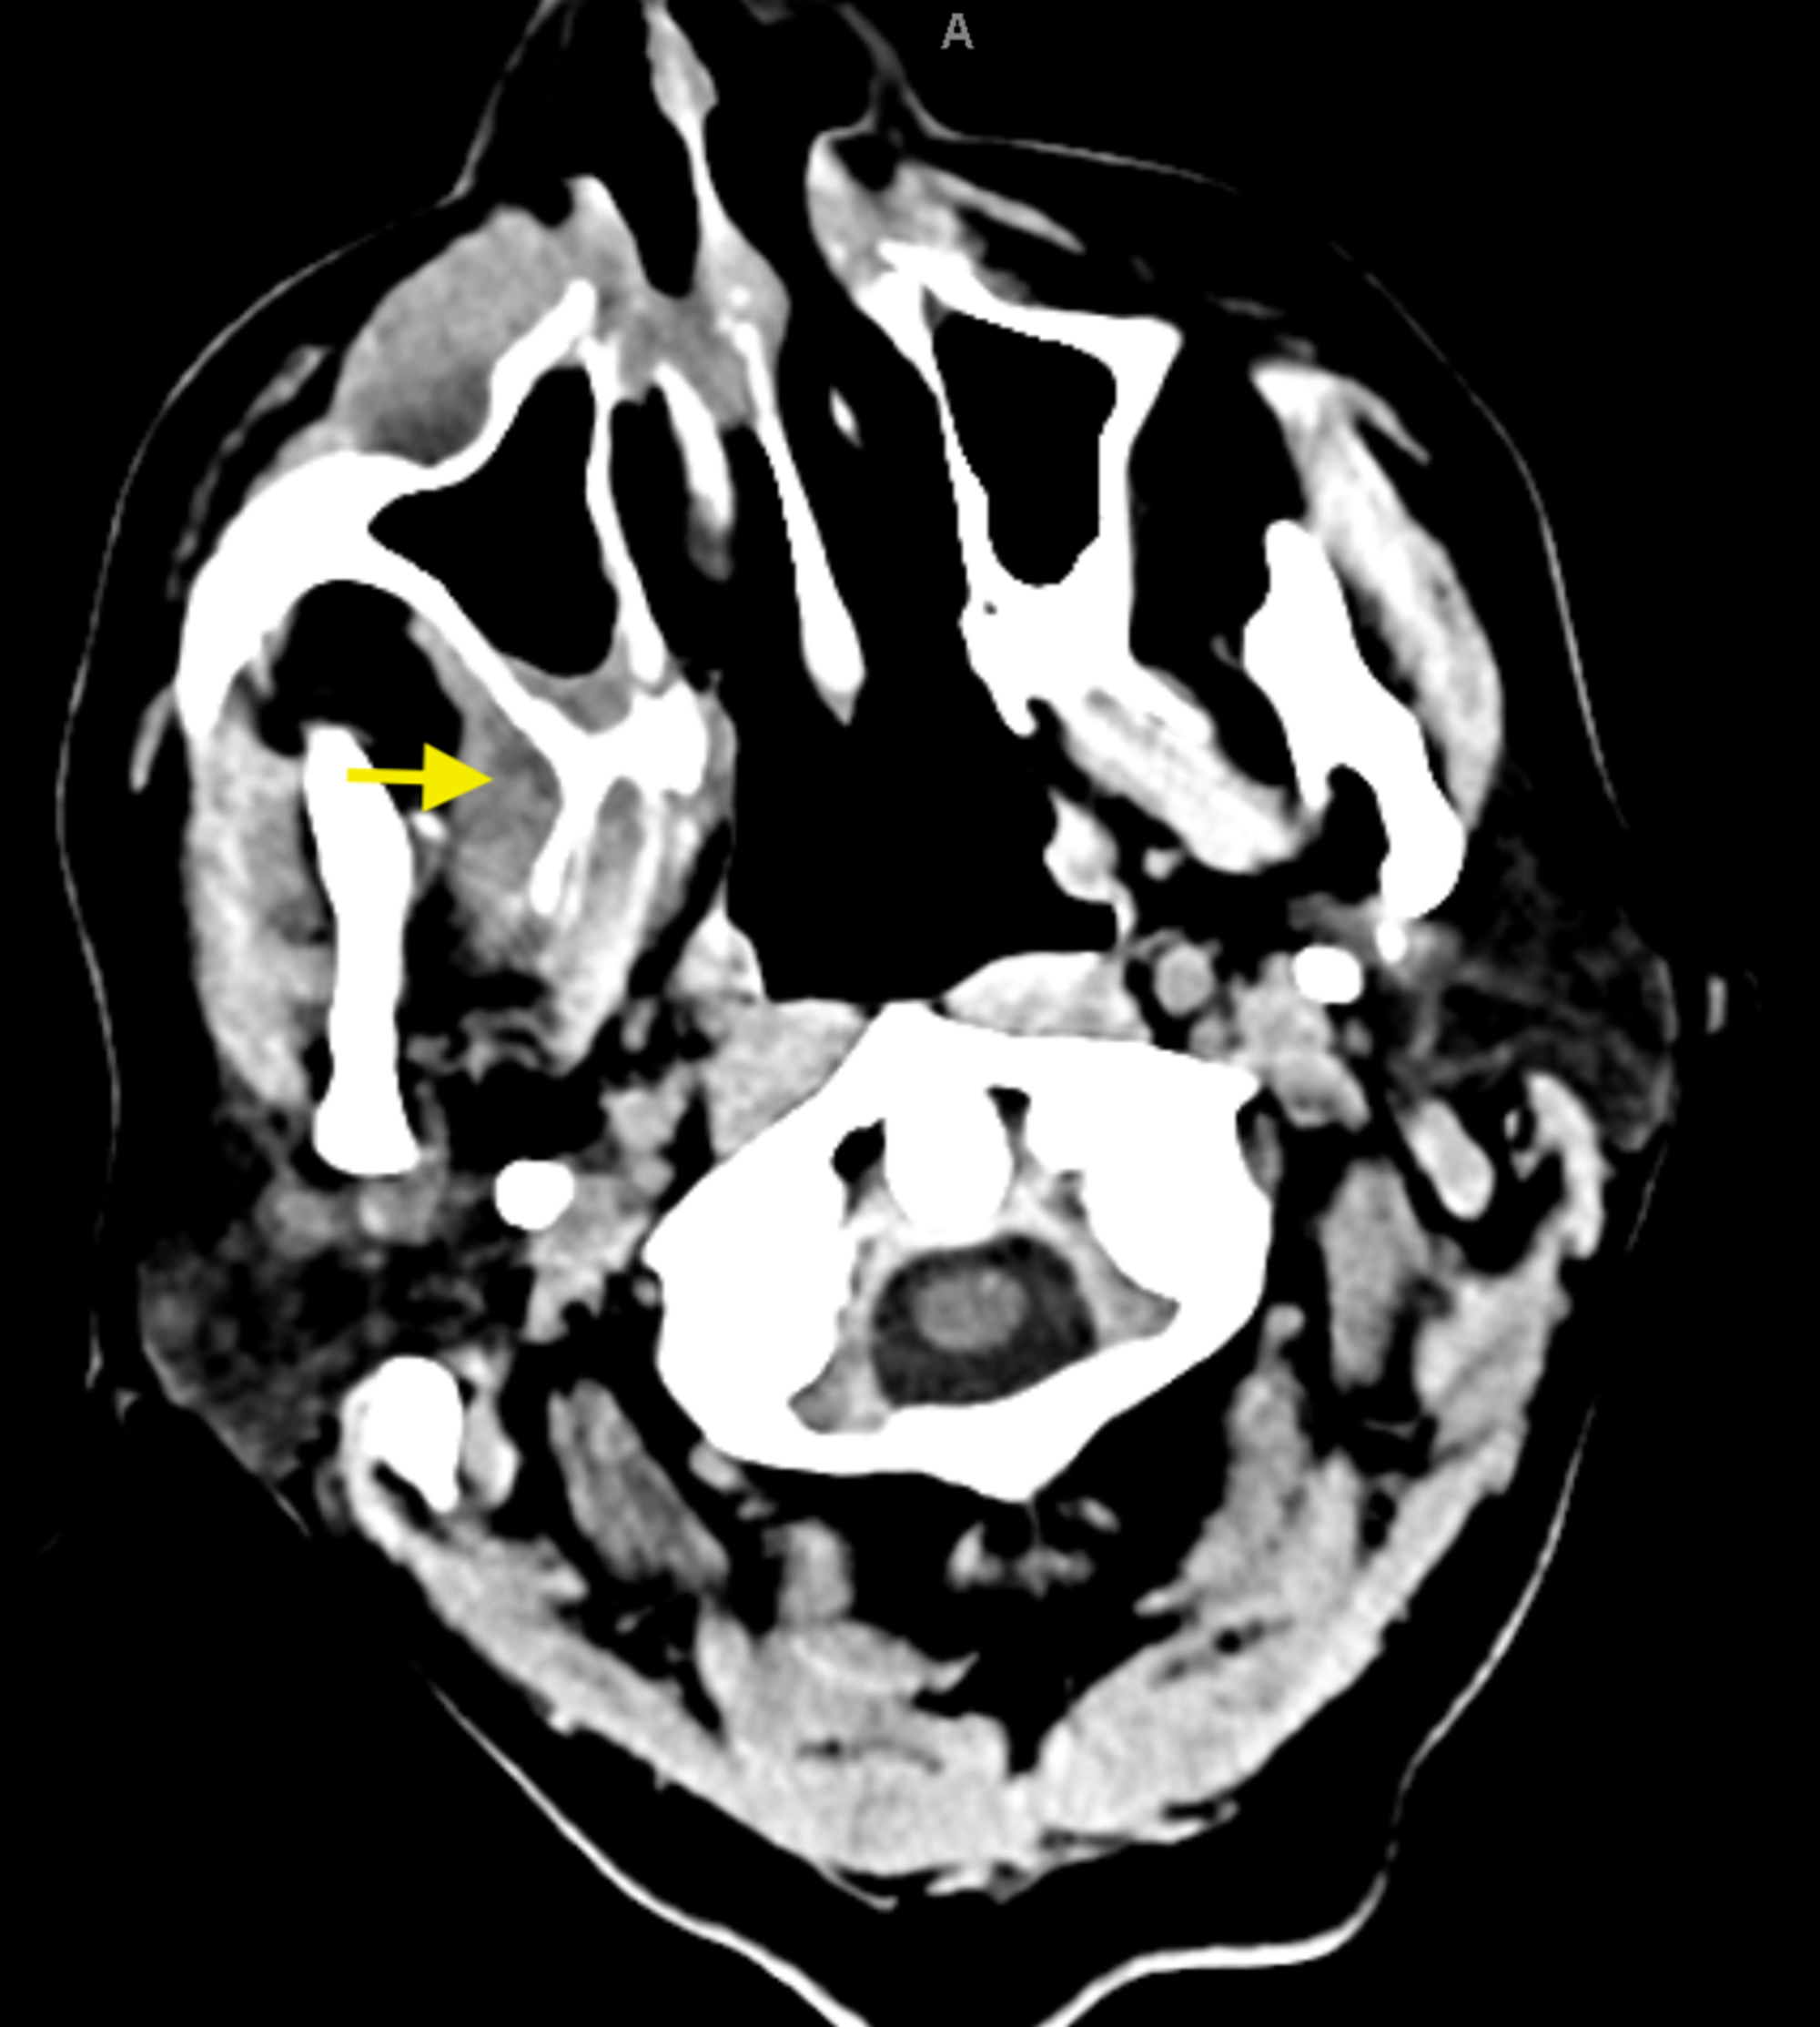

Chronic Osteomyelitis Radiology U of U School of Medicine Maxillary Osteomyelitis Symptoms  Web what are osteomyelitis symptoms? Web based on the clinical findings, a provisional diagnosis of chronic suppurative osteomyelitis of the maxilla was made. Web in established suppurative osteomyelitis, symptoms include deep pain, malaise, fever and anorexia. Web osteomyelitis should be suspected in those with a history of open fracture, recent orthopaedic surgery, or a discharging. The two predominant causes are. Maxillary Osteomyelitis Symptoms.

Dentistry and Medicine Osteomyelitiswith Radiological features Maxillary Osteomyelitis Symptoms  Web based on the clinical findings, a provisional diagnosis of chronic suppurative osteomyelitis of the maxilla was made. Signs and symptoms of osteomyelitis include: Web what are osteomyelitis symptoms? Osteomyelitis symptoms can vary depending on which type you have and which of your. The two predominant causes are odontogenic. Web osteomyelitis of the maxilla is now a rare event with. Maxillary Osteomyelitis Symptoms.